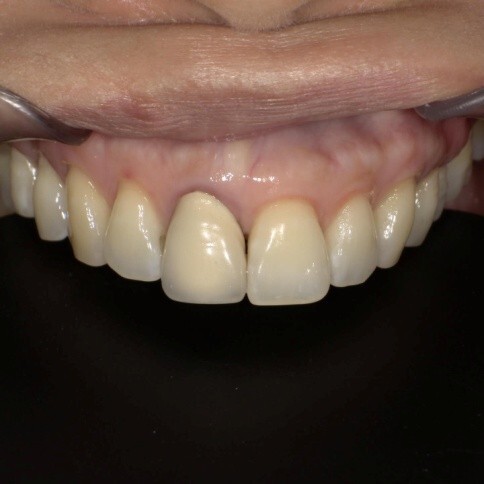

✨ 三、 四至六顆:微笑曲線重塑

Case 7:外突內收打造理想笑線,提亮色階。